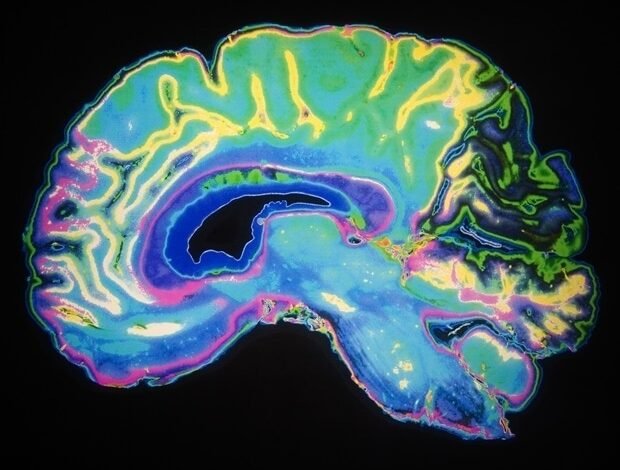

A equipe registrou a atividade nervosa dos micro eletrodos plantados na área do córtex cinético-a área do cérebro responsável por falar sobre quatro participantes com paralisia grave da esclerose lateral atrófica (ALS) ou AVC no tronco cerebral. Os pesquisadores pediram aos participantes que tentassem falar ou imaginar dizer um conjunto de palavras. Eles descobriram que a tentativa de falar e a fala interna estimulam as áreas entrelaçadas no cérebro e enriquecem padrões semelhantes de atividade nervosa, mas a fala interna tende a mostrar o tamanho da ativação em geral.